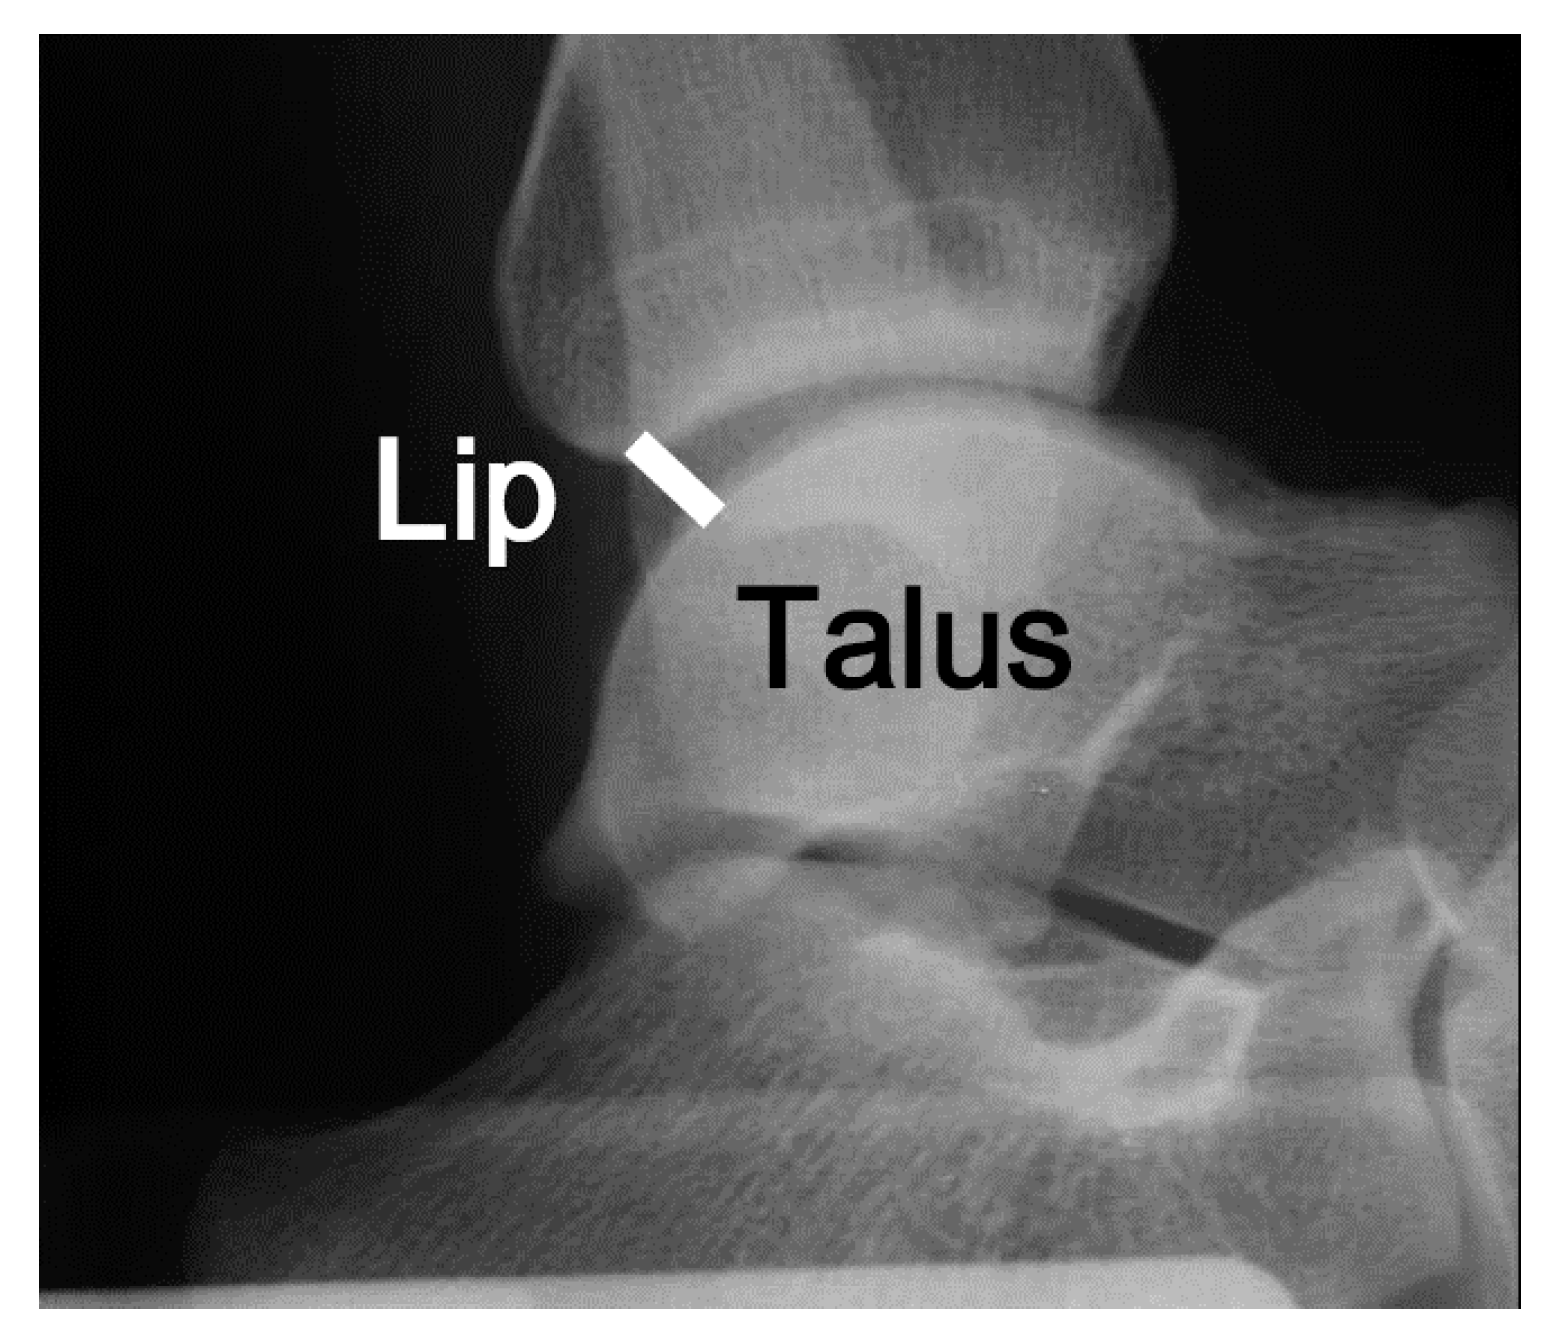

2.2.5. Measurement for the Stress Imaging Test